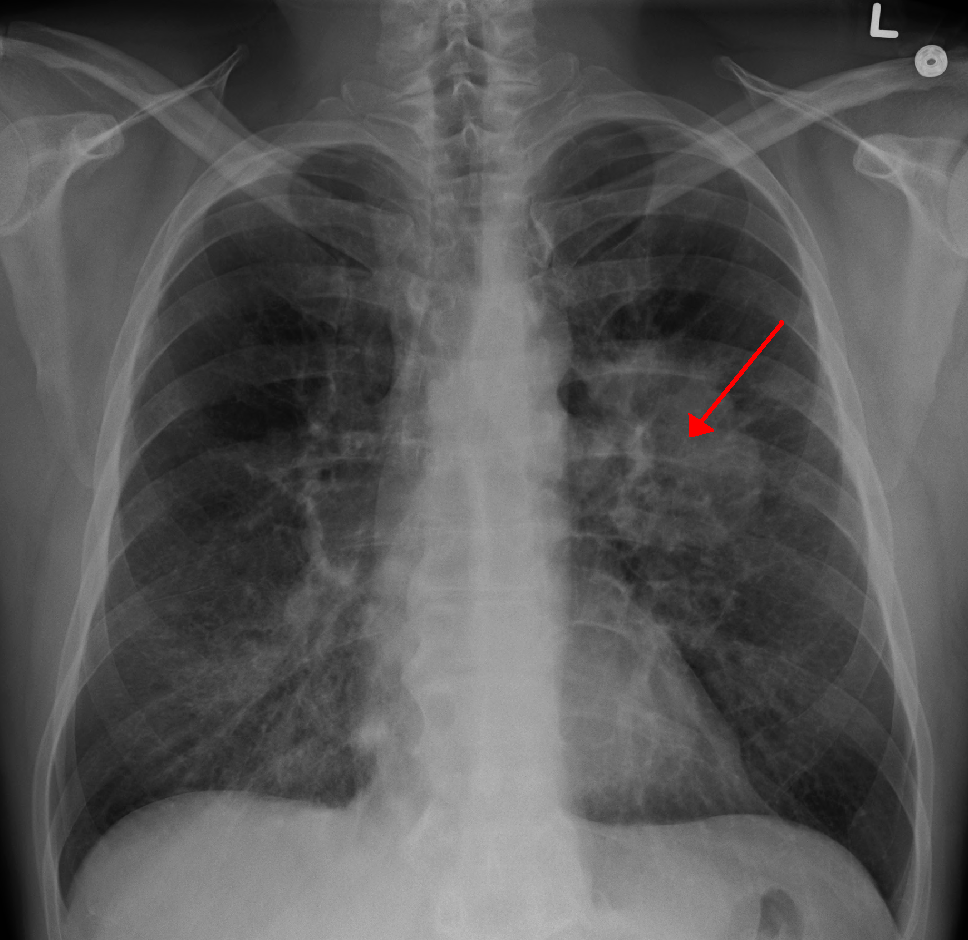

Szilasi Mária, a társaság alelnöke, a Debreceni egyetem (DE) tüdőgyógyászati klinikájának igazgatója kiemelte: napjainkban a férfiak és a nők tüdőrák-halálozási statisztikáját Európán belül Magyarország vezeti. A betegség elődleges rizikófaktora a dohányzás: hazánkban a felnőtt lakosság harmada cigarettázik rendszeresen, míg a daganatosok mintegy kilencven százaléka gyújt rá napi szinten.

A professzor a másik legjelentősebb tüdőgyógyászati betegségként a népbetegségnek számító COPD-t, a krónikus obstruktív tüdőbetegséget említette. A betegek száma évente 15 ezerrel emelkedik, összességében a megbetegedés csaknem félmillió embert érint hazánkban.